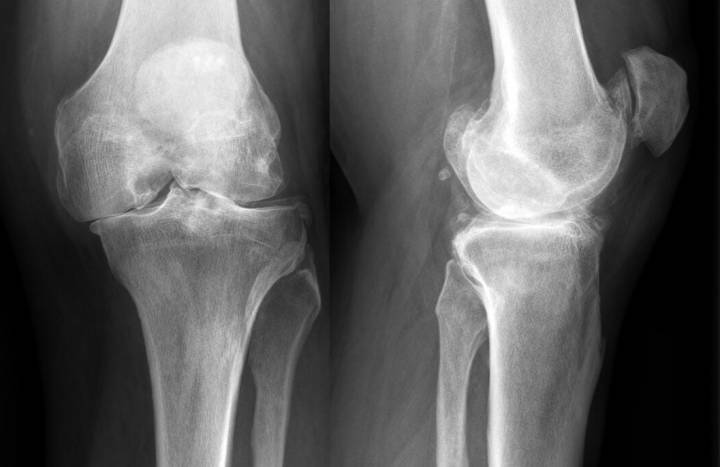

Een knieprothese is een vaak uitgevoerde behandeling voor gevorderde arthrose aan de knie. Knie-arthrose veroorzaakt pijn, voornamelijk bij stappen maar soms ook in rust. Daarnaast lukt het moeilijker om te stappen en trappen op en af te gaan. In deze gevallen is een prothese vaak aangewezen.

De "gouden standaard" voor de behandeling van gevorerde arthrose van de knie. Hierbij wordt het kapotte kniescharnier vervangen door een kunstgewricht. Bij een nieuwe knie operatie wordt een nieuw gewricht gecreëerd, door enkele millimeter kapot bot en kraakbeen weg te nemen en dit te vervangen door kunststof, zijnde metaal en poly-ethyleen (uitgeharde plastiek). Er bestaan verschillende technieken, waarbij de kruisbanden en de knieschijf kunnen vervangen of bewaard worden.

Vaak is het volledige gewricht aangetast en wordt geopteerd voor een vollledige veranging van het gewricht (totale knieprothese).

Mediale knieprothese

Indien slechts een deel van het gewricht aangetast is kan een gedeeltelijke prothese een oplossing zijn (partiële knieprothese). Hierbij wordt enkel het deel van de knie dat aangetast is vervangen door een prothese. Let wel: net zoals bij een totale knieprothese wordt zowel een stukje van het boven- en het onderbeen vervangen, en wordt er een tussenstuk geplaatst om de glijding tussen de 2 andere gedeelten te verbeteren. Het is dus niet zo dat enkel het boven- of onderbeen wordt vervangen.

Meestal is enkel de binnenzijde (= de mediale kant) aangetast en wordt enkel dit vervangen. Het voordeel van deze partiële prothese is dat het eindresultaat een natuurlijker gevoel geeft in vergelijking met een knieprothese. Ook zijn de complicaties en risico's van de procedure zelf een stuk geringer bij een partiële prothese in vergelijking met een totale prothese.

De radiografie en het onderzoek bepalen of deze ingreep mogelijk is. De resultaten van deze ingreep zijn goed zolang aan de juiste voorwaarden is voldaan, namelijk dat de aantasting zich beperkt tot de binnenzijde van de knie. Tijdens de operatie wordt steeds nagekeken of het correct is om een partiële prothese te plaatsen. Zo er aantasting van het andere compartiment wordt vastgesteld kan er onmiddellijk omgeschakeld worden naar een totale knieprothese.